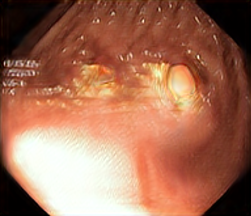

We have used a polyp dataset published with HyperKvasir dataset [51], which consists of polyp findings extracted from endoscopy examinations. HyperKvasir contains polyp images with corresponding segmentation masks annotated by medical experts. We use only this polyp dataset as a case study because of the time and resource-consuming training process of the SinGAN-Seg pipeline. However, the SinGAN-Seg model and pipeline can be used for any segmentation dataset.

A few sample images and the corresponding masks of the polyp dataset in HyperKvasir are shown in Fig 2. The polyp images are RGB images. The masks of the polyp images are single-channel images with white () for true pixels, which represent polyp regions, and black () for false pixels, which represent clean colon or background regions. In this dataset, there are different sizes of polyps. The distribution of polyp sizes as a percentage of the full image size is presented in the histogram plot in Fig 3, and we can observe that there are more relatively small polyps compared to larger polyps. Additionally, a subset of this dataset was used to prove that the performance of segmentation models trained with small datasets can be improved using our SinGAN-Seg pipeline, and the whole dataset was used to show the effect of using SinGAN-Seg generated synthetic images instead of a large dataset which has enough data to train segmentation models. In this regard, this dataset was used for two purposes: